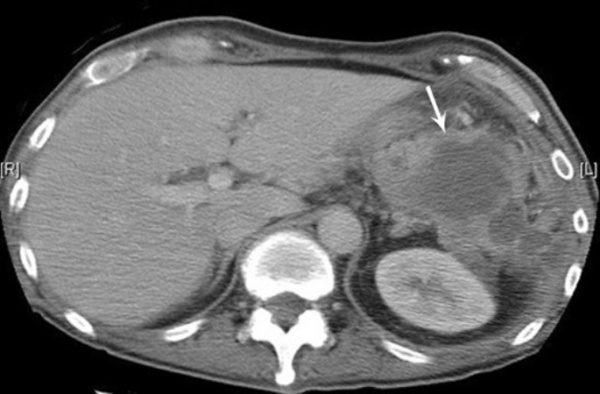

о Интрапаренхиматозный абсцесс (в печени, почках, селезенке и т. д.) часто проявляется отеком паренхимы со снижением ее плотности

(Слева) На аксиальной КТ с контрастным усилением у пожилой женщины после РХПГ и пап ил-лотомии визуализируется большое скопление газа и жидкости в забрюшинном пространстве, особенно в переднем околопочечном пространстве и в области межфасциальной пластинки.

(Справа) При аксиальной КТ с контрастом у этой же пациентки выявлен забрюшинный абсцесс. Перфорация произошла во втором отделе двенадцатиперстной кишки в зоне оперативного вмешательства (папиллотомии). (Слева) При аксиальной КТ с контрастным усилением у молодой женщины с прогрессирующей лихорадкой и болью в животе в течение многих дней определяется большой периаппендикулярный абсцесс, оказывающий объемное воздействие на тонкую кишку, мочевой пузырь и матку, смещающий их в сторону.